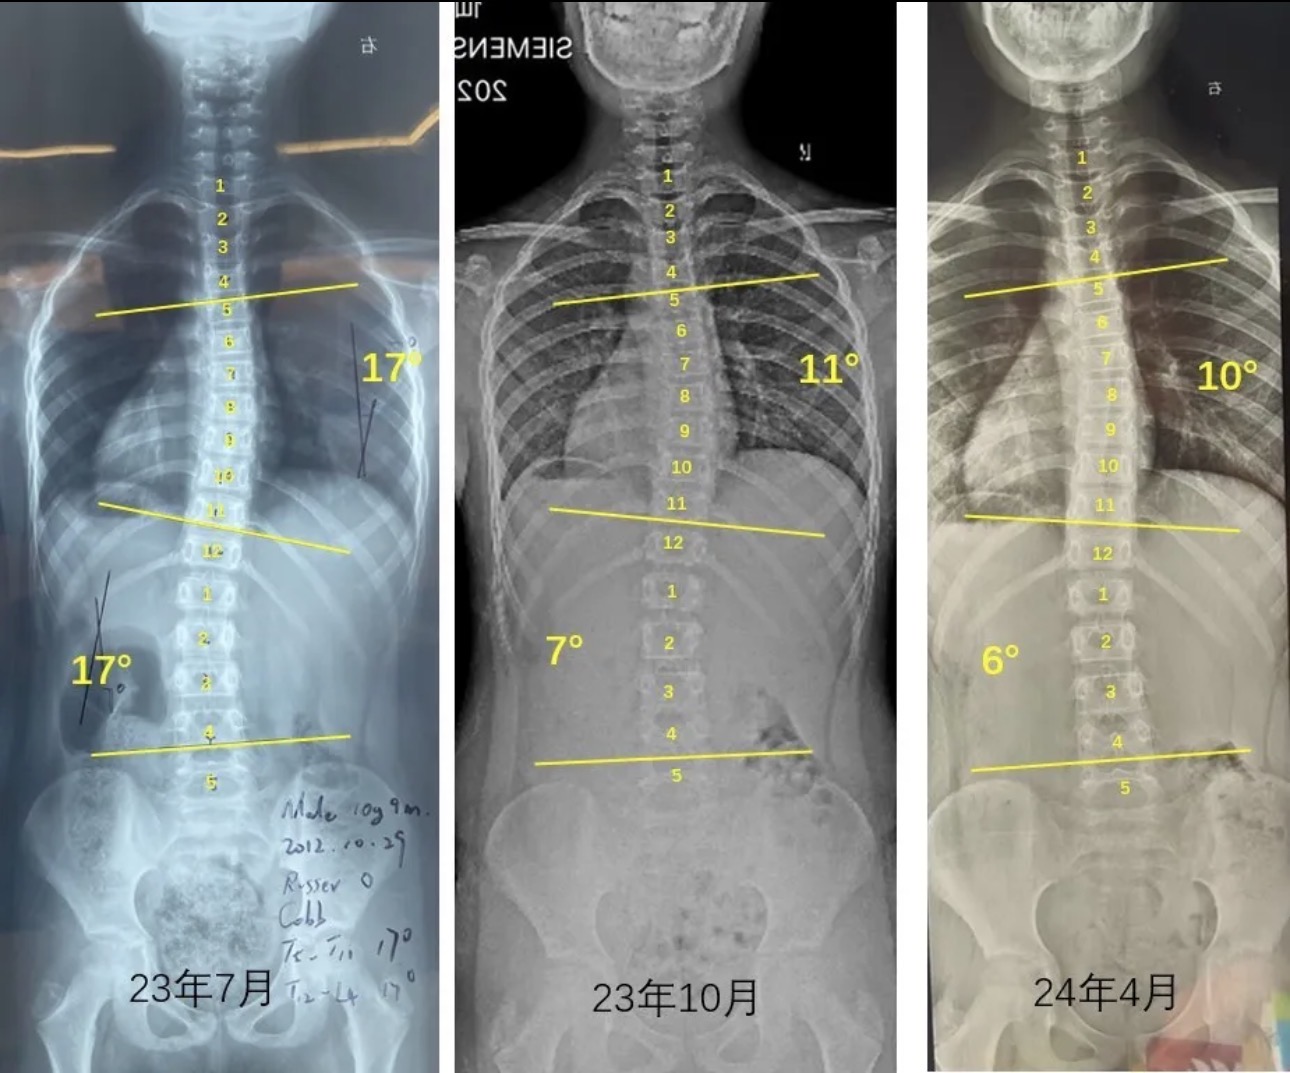

衷德脊柱,我们只关注侧弯保守治疗~

Zhongde Spine, bending no breaking ~